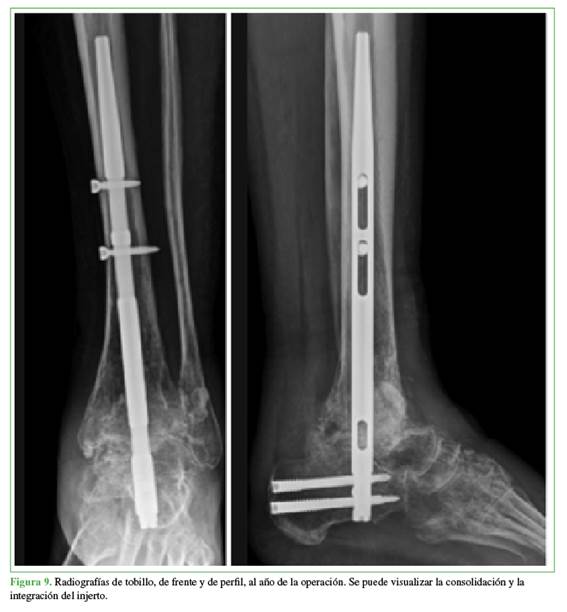

Se inmovilizó al paciente con una bota de yeso durante tres semanas para luego continuar con una bota walker sin carga. La carga parcial progresiva comenzó a los tres meses protegida con una bota walker y dos muletas. Se logró la consolidación a los ocho meses de la cirugía. El paciente pudo cargar, de manera completa, su miembro sin ningún tipo de asistencia a los 9.5 meses del segundo tiempo quirúrgico (Figura 9).

DISCUSIÓN